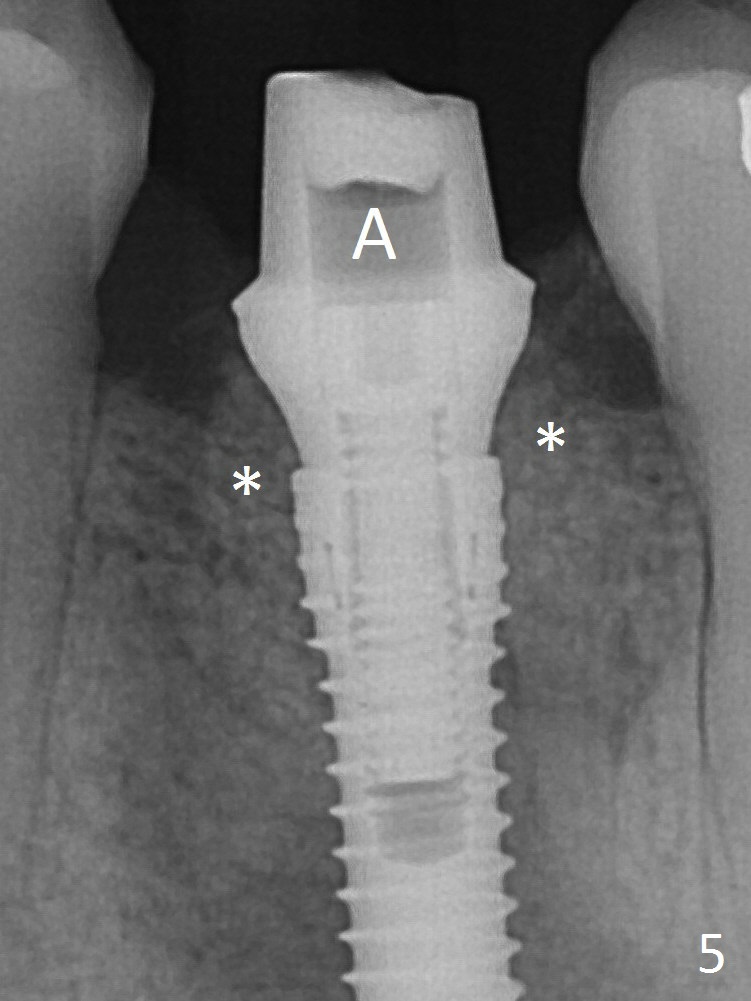

It appears that a 3.8x18 mm  implant is not placed deep enough.  Following 3-4 more turns of the implant and placement of a 5.5x4(3) mm abutment (Fig.5 A), allograft is placed (*).  The bone around the implant appears to have regenerated 4 months postop (Fig.7).